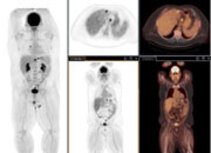

Übersicht PET-Schnitte Fusion

Bildfusion

Bei der Bildfusion werden die Bilddatensätze von PET und CT Akquisition übereinander gelegt. So kann die im PET-Bild enthaltene metabolische Information in Zusammenschau auf der anatomischen Informationen des CT-Bildes optimal befundet werden.